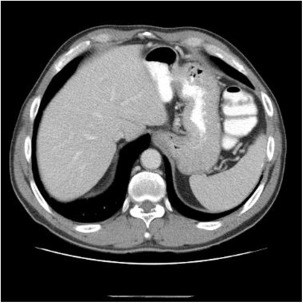

Проведенная эндоскопия показала небольшое варикозное расширение вен пищевода, тогда как визуализация печени (КТ брюшной полости) отсутствие любых видов очагового поражения или асцита (рис. 1).

На тот момент пациенту проводили лечение в соответствии с рекомендациями Европейской ассоциации по исследованию печени (EASL) c применением противовирусных препаратов прямого действия (ПППД): софосбувир 400 мг и велпатасвир 100 мг в сочетании с рибавирином длительностью 12 недель. Лечение проходило без каких-либо осложнений. Спустя три месяца после окончания лечения было зафиксировано достижение УВО.